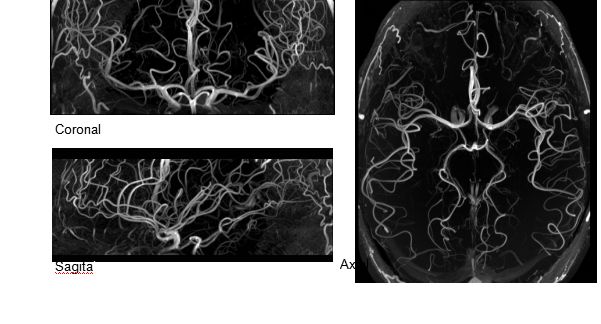

(TOF)300微米的各向同性分辨率顯示最小的血管

超精細(xì)的解剖細(xì)節(jié):T2對(duì)比

0.17 x 0.17 x 0.8毫米分辨率超高。

1毫米的各向同性分辨率DTI:神經(jīng)纖維束的交叉細(xì)節(jié)顯示

0.8毫米的各向同性分辨率:精確劃分灰質(zhì)和白質(zhì)

0.8毫米的各向同性分辨率:超精細(xì)的解剖細(xì)節(jié),例:小腦的精細(xì)結(jié)構(gòu)